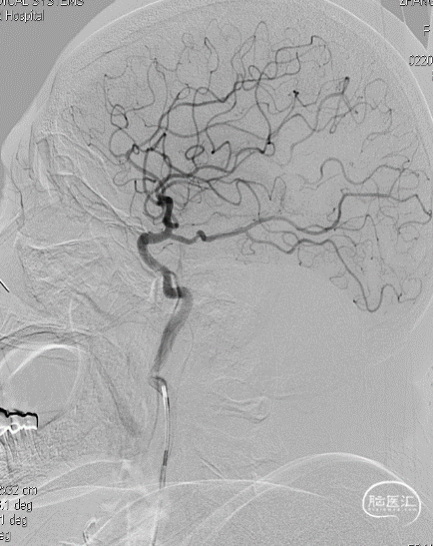

局麻,右股动脉入路置8F短鞘,导管导丝技术将8F MPA置于右C1末端,造影确认右M1急性闭塞,侧支代偿差。

以Transend导丝 + Headway21导管到达M1中段,Sofia PLUS顺畅到位(M1中段),ADATP技术抽吸取栓,一次成功取通,前向血流恢复至TICI3级,无栓子逃逸及原位狭窄,穿刺至开通时间20min(患者术中间断躁动不配合)。

开通右MCA后,行左侧颈动脉及左椎动脉造影显示血流通畅(双侧后交通动脉开放)。

右颈动脉再次造影见前向血流持续通畅,患者此时左侧下肢肌力恢复Ⅲ级、上肢Ⅰ级、语言功能好转,遂结束手术。

以Sofia Plus进行抽吸取栓1次(ADAPT技术),实现血流复通(TICI 3级)